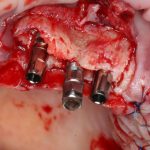

Кстати, обрати внимание на ширину альвеолярного гребня (левая картинка). Она чуть меньше 3 мм. Это объясняет, почему я засомневался в возможности установки имплантатов одновременно с остеопластикой. Понятно и без КЛКТ.

Возвращаемся к основной операционной области. Еще раз посмотрим на альвеолярный гребень, поофигеваем от его ширины и моих грандиозных планов:

Я зафиксировал костный блок практически без адаптации на несколько винтов. Обрати внимание, что винты находятся в зоне, где не планируется установка имплантатов. Фиксация должна быть надежной, поскольку мне еще предстояла подготовка лунок для имплантатов. Трех винтов для этого вполне достаточно.

Напомню, что для этой работы я выбрал субкрестальные имплантаты Ankylos C/X. Они прекрасно сочетаются с любым методом остеопластики.

Глянем на то, что получилось: